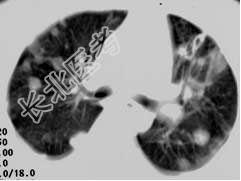

- 单项选择题女,32岁, 鼻梁双颊部出现红斑伴发热咳嗽2周,肘腕关节游走性疼痛, 结合CT图像,最可能的诊断为 ( )

D、SLE肺部浸润